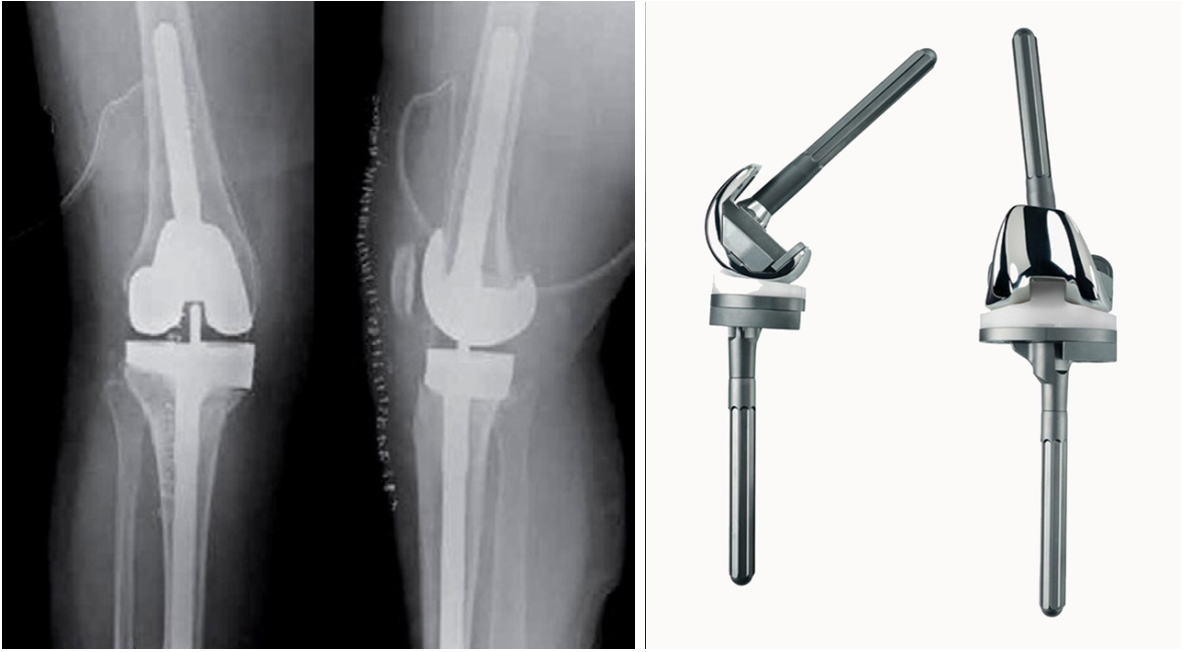

假体示意图

膝关节假体翻修通常有不同程度的骨缺损,使用表面关节难于获得良好固定,股骨侧和胫骨测必须加延长杆才能获得良好固定,目前多个厂家均生产类似产品。单纯性的增加稳定性假体的限制性较多,通过延长杆以提升稳定度,其适用于关节韧带功能较优的患者,而那些股骨、胫骨端发育不良、病变等情况的患者则不适用。